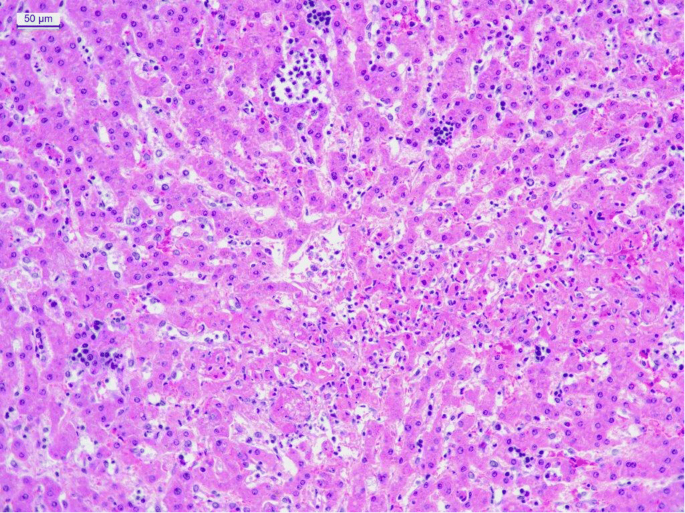

Микрофотографии гистологии глиобластомы головного мозга